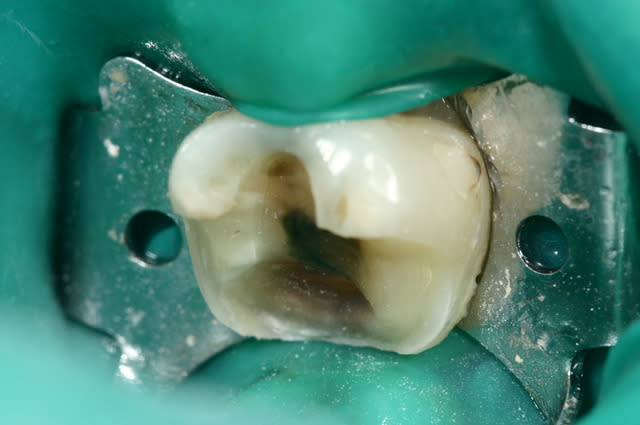

tes photos sont excellentes!

Il faut toujours essayer : parfois on est un peu sous gingival , ça à l'air mal barré et puis on met la digue et hop : magie !!! cf photo ci-joint.

Digue si6cja - Eugenol